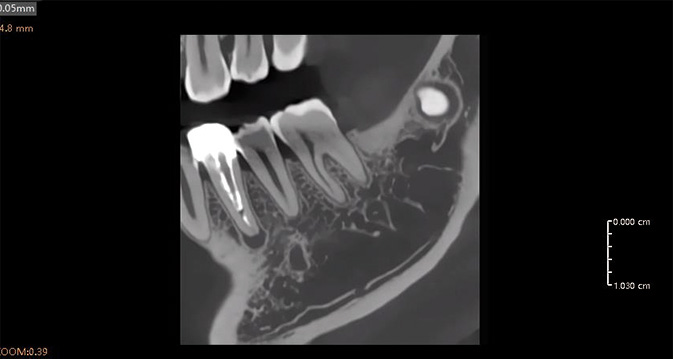

Resolución de Voxel HD de 50 µm

La resolución de vóxel ultrafina garantiza una nitidez de grado clínico para diagnósticos de precisión y planificación quirúrgica.

Generador de Alto Voltaje de 120 kV

Imágenes de alta energía para una salida estable y ruido reducido, asegurando claridad incluso en anatomías desafiantes.

Análisis Endodóntico Impulsado por IA

El módulo de endodoncia de IA detecta y aísla automáticamente cada diente, proporcionando tres modos de visualización 3D: superficie, conducto radicular y transparencia. Esto permite una observación precisa de la morfología, el número y el detalle del conducto radicular, ayudando a los clínicos a realizar diagnósticos y mediciones precisas con facilidad.

Tratamiento y Cirugía de Implantes Impulsados por IA

Herramienta de Planificación de Implantes por IA

La herramienta de planificación impulsada por IA detecta automáticamente los dientes y el nervio alveolar inferior, proporcionando alertas de seguridad en tiempo real. Soporta medición automática, simulación de implantes y optimización de trayectoria, lo que permite una planificación de tratamiento rápida y precisa.